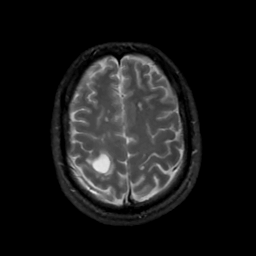

MR Study #6, March 17, 1991 -- Slice #39

[Home][Help][Clinical][Tour 1][Tour 2] Slice 39